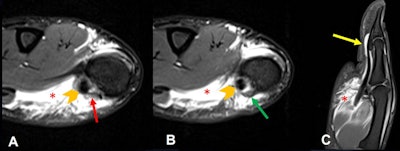

MRI is the best modality for diagnosis and evaluation of soft-tissue trauma in the hand and wrist, particularly in the PIP and MCP joints, and it is useful for evaluating acute and chronic lesions of the stabilizing articular elements (volar plate and collateral ligaments) of the fingers and thumbs, including injuries to the pulley system, they stated.

Dislocations (dorsal, volar, or lateral) are common in ball-handling sports. Dorsal is the most common type, often involving hyperextension with axial loading. Volar plate injuries occur at the distal attachment with/without avulsion fracture of the base of the MCP joint.

Volar (straight volar, lateral volar, or rotatory) may involve force coupled with a volar thrust to the middle phalanx, and fractures/dislocations have a similar mechanism to dorsal dislocation. Volar plate injuries can be isolated or may occur in association with other injuries, such as collateral ligament tears, the researchers explained.

In the thumb, CMC joint injuries often are associated with fractures (e.g., Bennett's fracture). Dislocation without fracture is rare and involves rupture of the volar beak ligament with dorsal displacement of the first metacarpal, the authors noted.

Common injuries to the thumb MCP joint include dorsal dislocations (hyperextension with complete rupture of the volar plate, usually proximally), collateral ligament injuries, and skier's or gamekeeper's thumb (radially directed force on an abducted thumb), they continued.